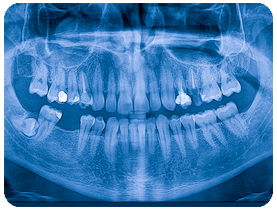

Full Diagnostic X-rays

Our office has the capacity to take a complete series of diagnostic X-rays of your mouth to allow our dentists to identify oral problems that would be undetectable by a visual examination. We employ the use of digital panoramic X-ray and digital bitewing X-ray machines to obtain a complete picture of your teeth, gums and oral cavity.

Thanks to new digital technology, we can take X-rays of your mouth that use 90 percent less radiation that standard film X-rays. In addition, digital X-rays are immediately transmitted to a computer screen in our treatment room, so you don’t have to spend your valuable time waiting for your X-rays to be developed. Instead, you can see the images of your teeth instantly, and computer technology allows the X-rays to be enlarged, highlighted, inverted or even colorized, helping you and your dentist see hard-to-spot dental problems.